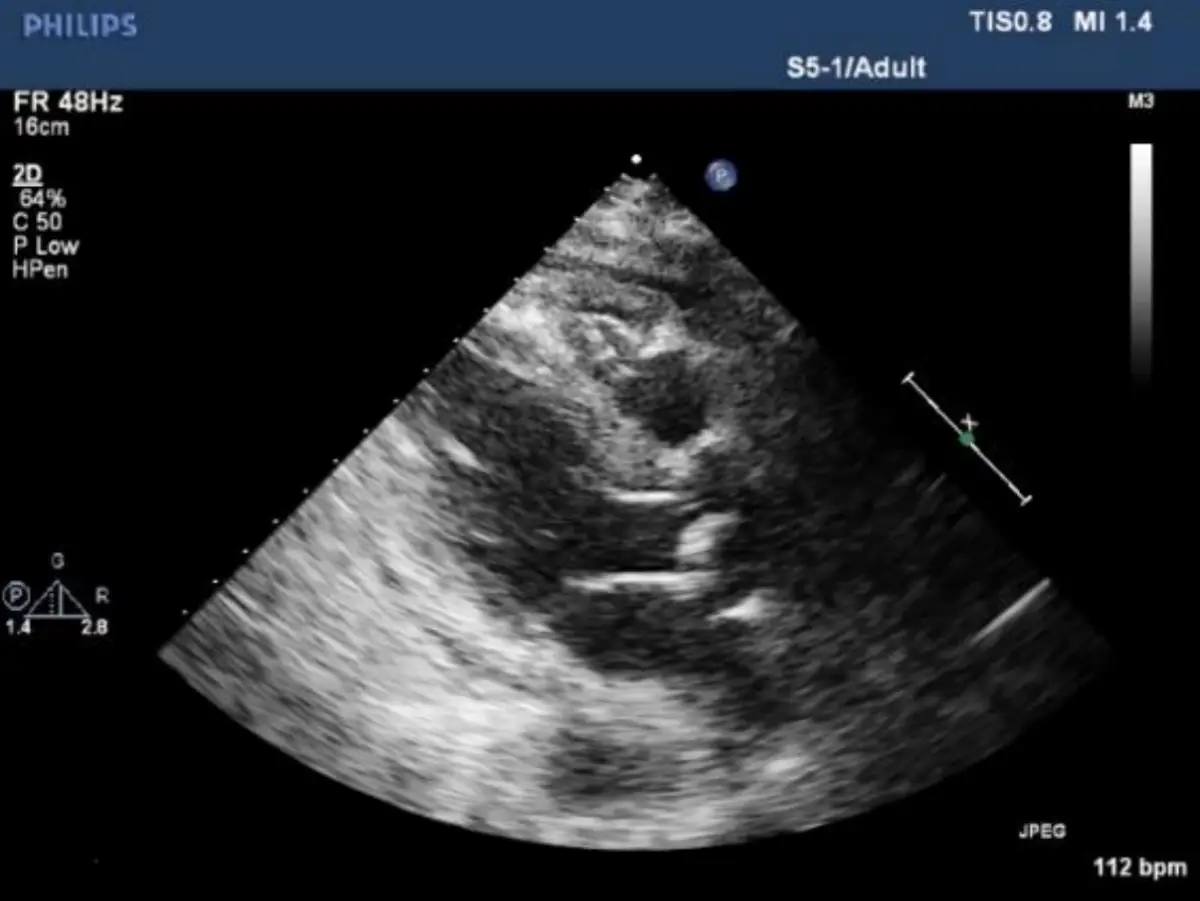

病人王先生現年88歲,有兩個月的雙腳浮腫及運動性呼吸困難,數度前往多家醫院求診,診療罔效。病人 有多年高血壓、高脂血、慢性腎臟病及前列腺肥大等過往病史。到診時意識清醒, T/P/R: 35.5 °C/99/18; BP: 106/83 mmHg; SpO₂: 92%。(ambient air); BH: 165 cm; BW: 66 kg; BMI: 24.2 kg/m² 理學檢查發現 顏面微腫,頸靜脈中度怒張,脈搏稍弱,並未有顯著Paradoxical pulse, 及Kussmaul sign,呼吸聲清 淨,心臟大小正常,心音略遠,P2稍強,Pericardial friction可疑,無肝、脾腫大,雙腳微腫。其心電 圖、胸部X光及其他影像檢查如圖:請問依照上列數個標的之理學檢查 (Targeted physical examination) 及實驗室所見,這位病人最可能的診斷是

心包積液及心臟壓塞(cardiac tamponade)的臨床表現、電圖特徵與多模態影像診斷。

影像分析:

- 胸部X光:心影擴大呈「水瓶狀」輪廓,心臟外形圓鈍平滑,肺野無明顯充血或水腫,符合大量心包積液造成的心影變化(en.wikipedia.org)